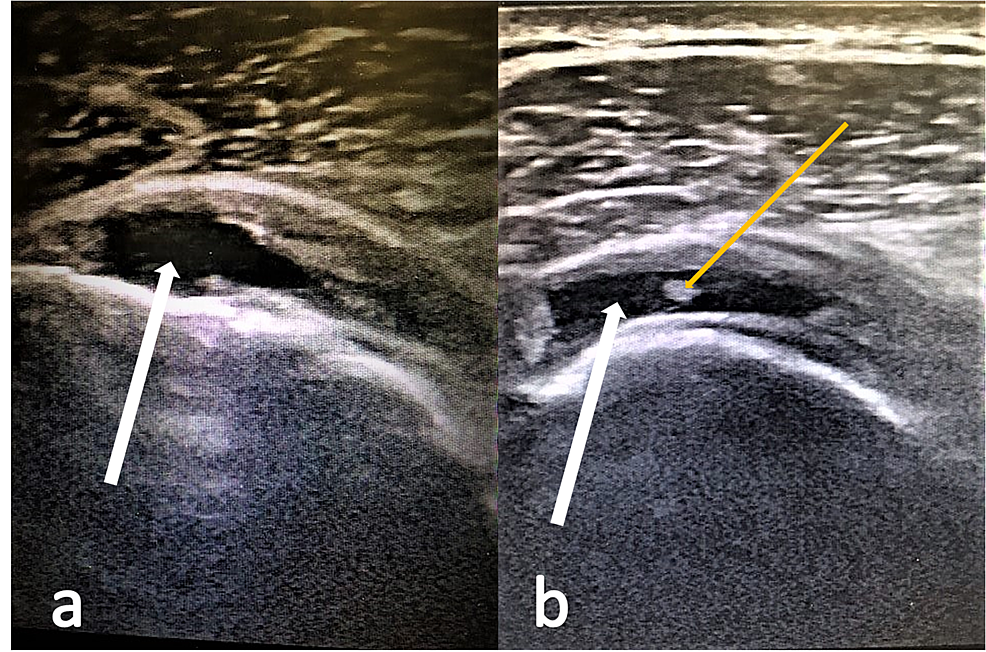

From obgynkey.com

Color Doppler in Fetal Echocardiography Obgyn Key What Does Yellow Mean On Ultrasound ultrasounds are valuable in healthcare to visualize internal organs and tissues. what do yellow or orange mean on an ultrasound? yellow or orange color. reading an ultrasound can be easy if you know what meaning to assign to the text and numbers, images, and colors. power doppler is an ultrasound modality, which uses only the. What Does Yellow Mean On Ultrasound.